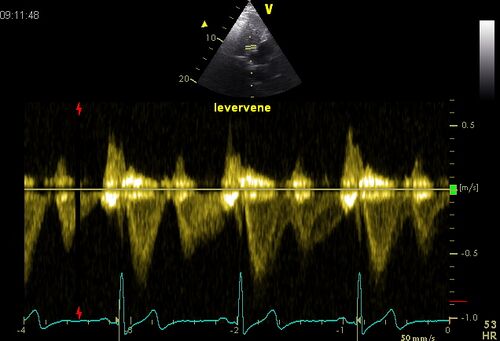

Hepatic vein flow

Pulsed Doppler signal of hepatic vein in severe tricuspid insufficiency.

Holosystolic retrograde flow in the hepatic vein indicates TI hemodynamically important. At greatly increased RA retrograde flow may be lacking in the hepatic vein, despite serious Tl.